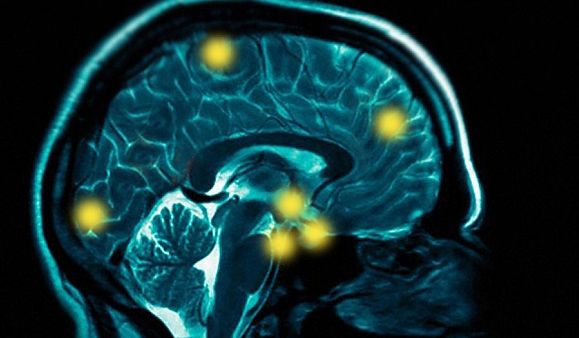

Ecco come il nostro cervello sincronizza comandi provenienti da diverse aree nervose.

Onde cerebrali «sincronizzano» alcune aree nervose con la vista e ci consentono di compiere azioni che richiedono estrema precisione anche quando siamo distratti

OCCHI E CERVELLO – Ogni istante una quantità impressionante di informazioni visive colpisce i nostri occhi, ma nella maggior parte dei casi siamo in grado di concentraci solo sui dettagli di nostro interesse. Per restare nella metafora automobilistica, quando ci troviamo in un luogo sconosciuto e siamo sprovvisti di GPS l’attenzione si rivolge principalmente ai cartelli stradali e alle possibili fonti di indicazione, tralasciando qualsiasi elemento di contesto, come potrebbero essere gli alberi sul ciglio della strada, la spazzatura sui marciapiedi o i pedoni che ci passano a fianco. Alcuni scienziati del Massachusetts Institute of Technology hanno scoperto che questo indirizzamento dell’attenzione dipende da onde cerebrali ad alta frequenza che interconnettono il centro di controllo del cervello al centro visivo. Finora, infatti, era risaputo che all’interno del processo di concentrazione un ruolo importante fosse giocato dalla corteccia prefrontale, ma le conoscenze su come questa agisse erano ancora scarse, dal momento che è situata agli antipodi del cervello rispetto al centro di controllo della vista. Ora, grazie allo studio condotto dal neuroscienziato Robert Desimone, si è scoperta una perfetta sincronia tra il sistema sensoriale e quello cerebrale.

STIMOLAZIONI SINCRONIZZATE – La ricerca è partita dall’analisi dell’attività neuronale di due scimmie, concentrate nella visualizzazione di un’immagine sullo schermo di un PC. Come si aspettavano, gli scienziati hanno osservato che la stimolazione dei neuroni dell’area visiva produceva segnali elettrici sincronici. Ciò che invece ha colto tutti di sorpresa, è stata la scoperta dell’attività di alcuni neuroni della corteccia prefrontale con la stessa identica frequenza. Ad un’analisi più approfondita, si è scoperto che la trasmissione del segnale aveva inizio proprio da questa regione centrale e solo dopo una decina di millisecondi veniva emulata dall’attivazione dei neuroni della corteccia visiva: il tempo, dunque, che le onde ad alta frequenza mettessero in comunicazione le due regioni per consentire un’azione in perfetta sincronia. In conclusione, sono i neuroni nella corteccia prefrontale a governare l’attivazione di quelli nella regione visiva cosicché l’attenzione possa essere interamente indirizzata sull’immagine che richiede particolare concentrazione.